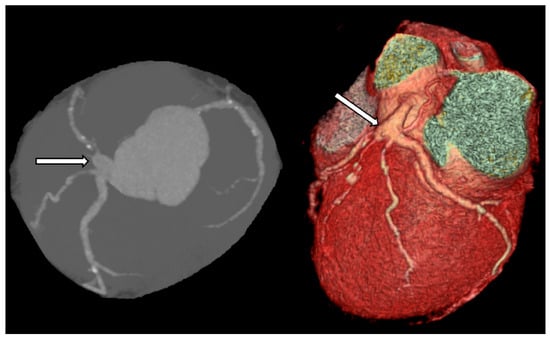

Coronary computed tomography (CT) is a noninvasive method that enables accurate assessment of aneurysm size and location. It also allows for the evaluation of the amount of thrombus and calcification within the aneurysm (Figure 7). Multidetector computed tomography (MDCT) is particularly helpful in preoperative planning, as it depicts spatial relations of the aneurysm and other structures located nearby [,].

Figure 7. The aneurysmal lesion (arrow) of the left main coronary artery in CT.